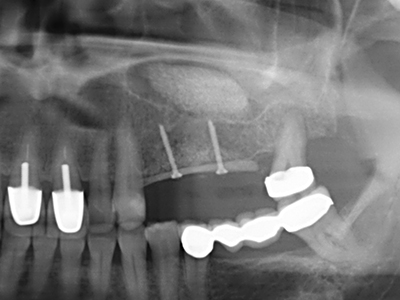

Fig. 15: El control radiológico realizado al cabo de un año muestra una estabilidad del nivel óseo.

Fig. 16: También condiciones intraorales estables con incorporación de los implantes en la encía queratinizada.